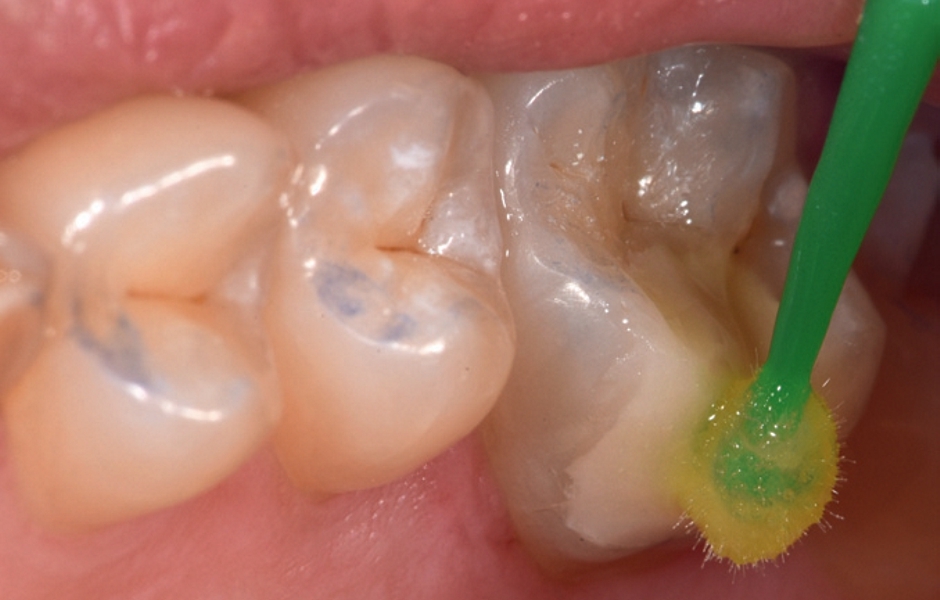

Posílení a znecitlivění pomocí GC Tooth Mousse, GC MI Paste Plus a MI Varnish

Lokální léčba těmito preparáty je užitečná pro posílení a snížení citlivosti zubů při MIH. Obsahují Recaldent (CPP-ACP) s vysokým podílem biologicky dostupného vápníku a fosfátu, jehož aplikace se v tomto případě prokázala jako účinná4, 5 k redukci porozit a zlepšení homogennosti hypomineralizované skloviny. Příprvek Tooth Mousse bez obsahu fluoridu se doporučuje pro děti do 6 let a MI Paste Plus s 900 ppm fluoridu ro děti od 12 let. MI Varnish (22600 ppm fluoridu) je ochranný lak určený k ambulantní aplikaci jednou za čtvrt roku po profylaktickém čištění zubů k těsnému zapečetí dentálních tubulů a znecitlivění zubů.